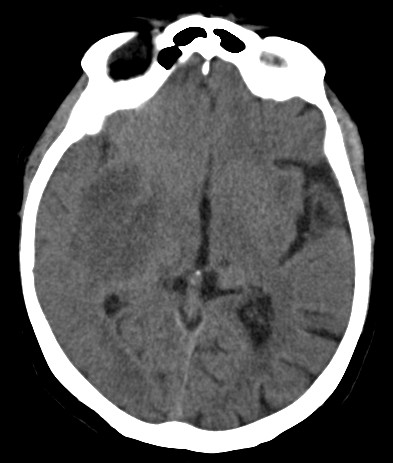

Implementing a CT slice viewer

The Computed Tomography (CT) DICOM files contain both data => Hounsfield Units (HU) matrices, and metadata => information on patients, CT scanner used, etc. The HU scale represents a linear transformation of the X-Rays attenuation coefficient μ. Thus, distilled water at standard pressure and temperature (STP) is defined as 0 HU, while the radiodensity of air at STP is defined as −1000 HU.

For viewing CT slices, one needs to transform it into a grayscale Bitmap image. The first step is applying a linear transformation, as bitmaps are limited to 256 values.

Try generating the bitmap for various HU windows.

It is important to note the difficulties in viewing/understanding the whole information contained in one HU matrix.